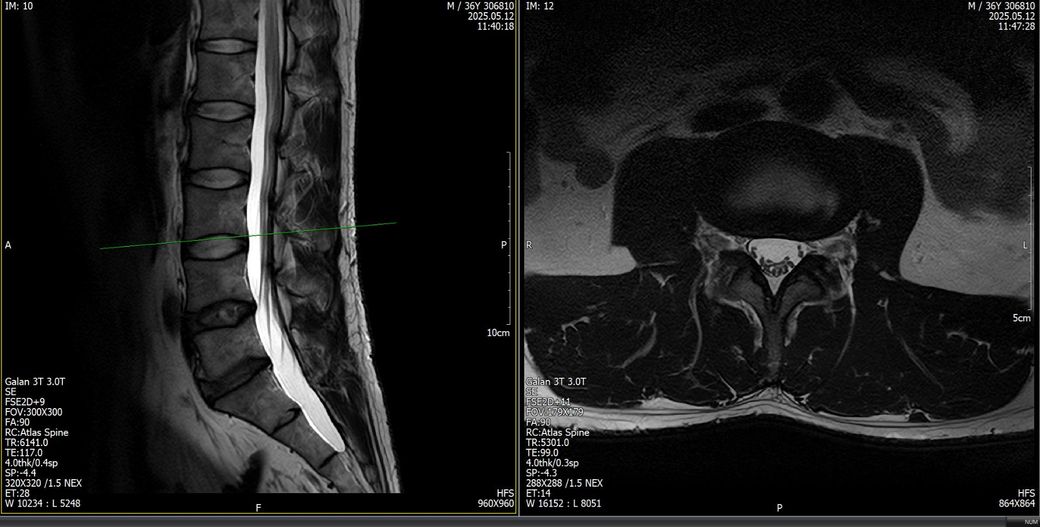

문제는 상체에서 끝나는게 아니라 3월중순쯤 길을 걷는데 발바닥 아치에서 모레알 밟는느낌이 나더니 이게 보름정도 지나고나서 양측성으로 나타나면서 모레알 밟는 감각이상의 느낌이 열감으로 바뀌더니 작열감으로 또 변질되고 앞꿈치 뒷꿈치 막 퍼지듯 하면서 왼쪽정강이쪽엔 벌레기어가는 그런느낌들고 허벅지에 따끔한 증상같은게 올라오고 엉치통증 허리통증 이런식으로 올라와서 허리문젠가 싶어서 mri를 찍어봣는데 목이나 허리나 퇴행변성같은게 포착이 되었지만 그게 신경을 누르는 상태는 또 아니였습니다. 허리와 목 mri 사진을 혹시 몰라서 첨부합니다.

목은 25년2월에 찍었고 허리는 25년5월,7월 2번을 연달아 찍었습니다. 왜냐면 하체증상으로 더 심하게 느낀 상태였기 떄문에